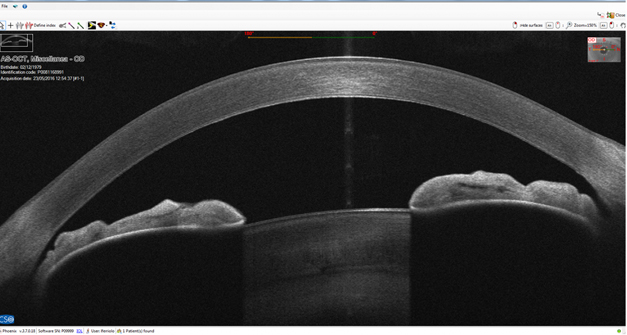

HD ANTERIOR SEGMENT & CHAMBER

High-resolution section images on a diameter of 16 mm

CORNEAL SECTION

The sharpness of the high-resolution section images on a diameter of 16 mm, together with the many details of the structure and the cornea layers brought to light by the instrument, are the most extraordinary features and appreciated by the specialists of the anterior segment (corneal and epithelial). The device provides pachymetry, elevation, curvature and power information for both corneal surfaces down to an unequalled 3.5µ of precision.